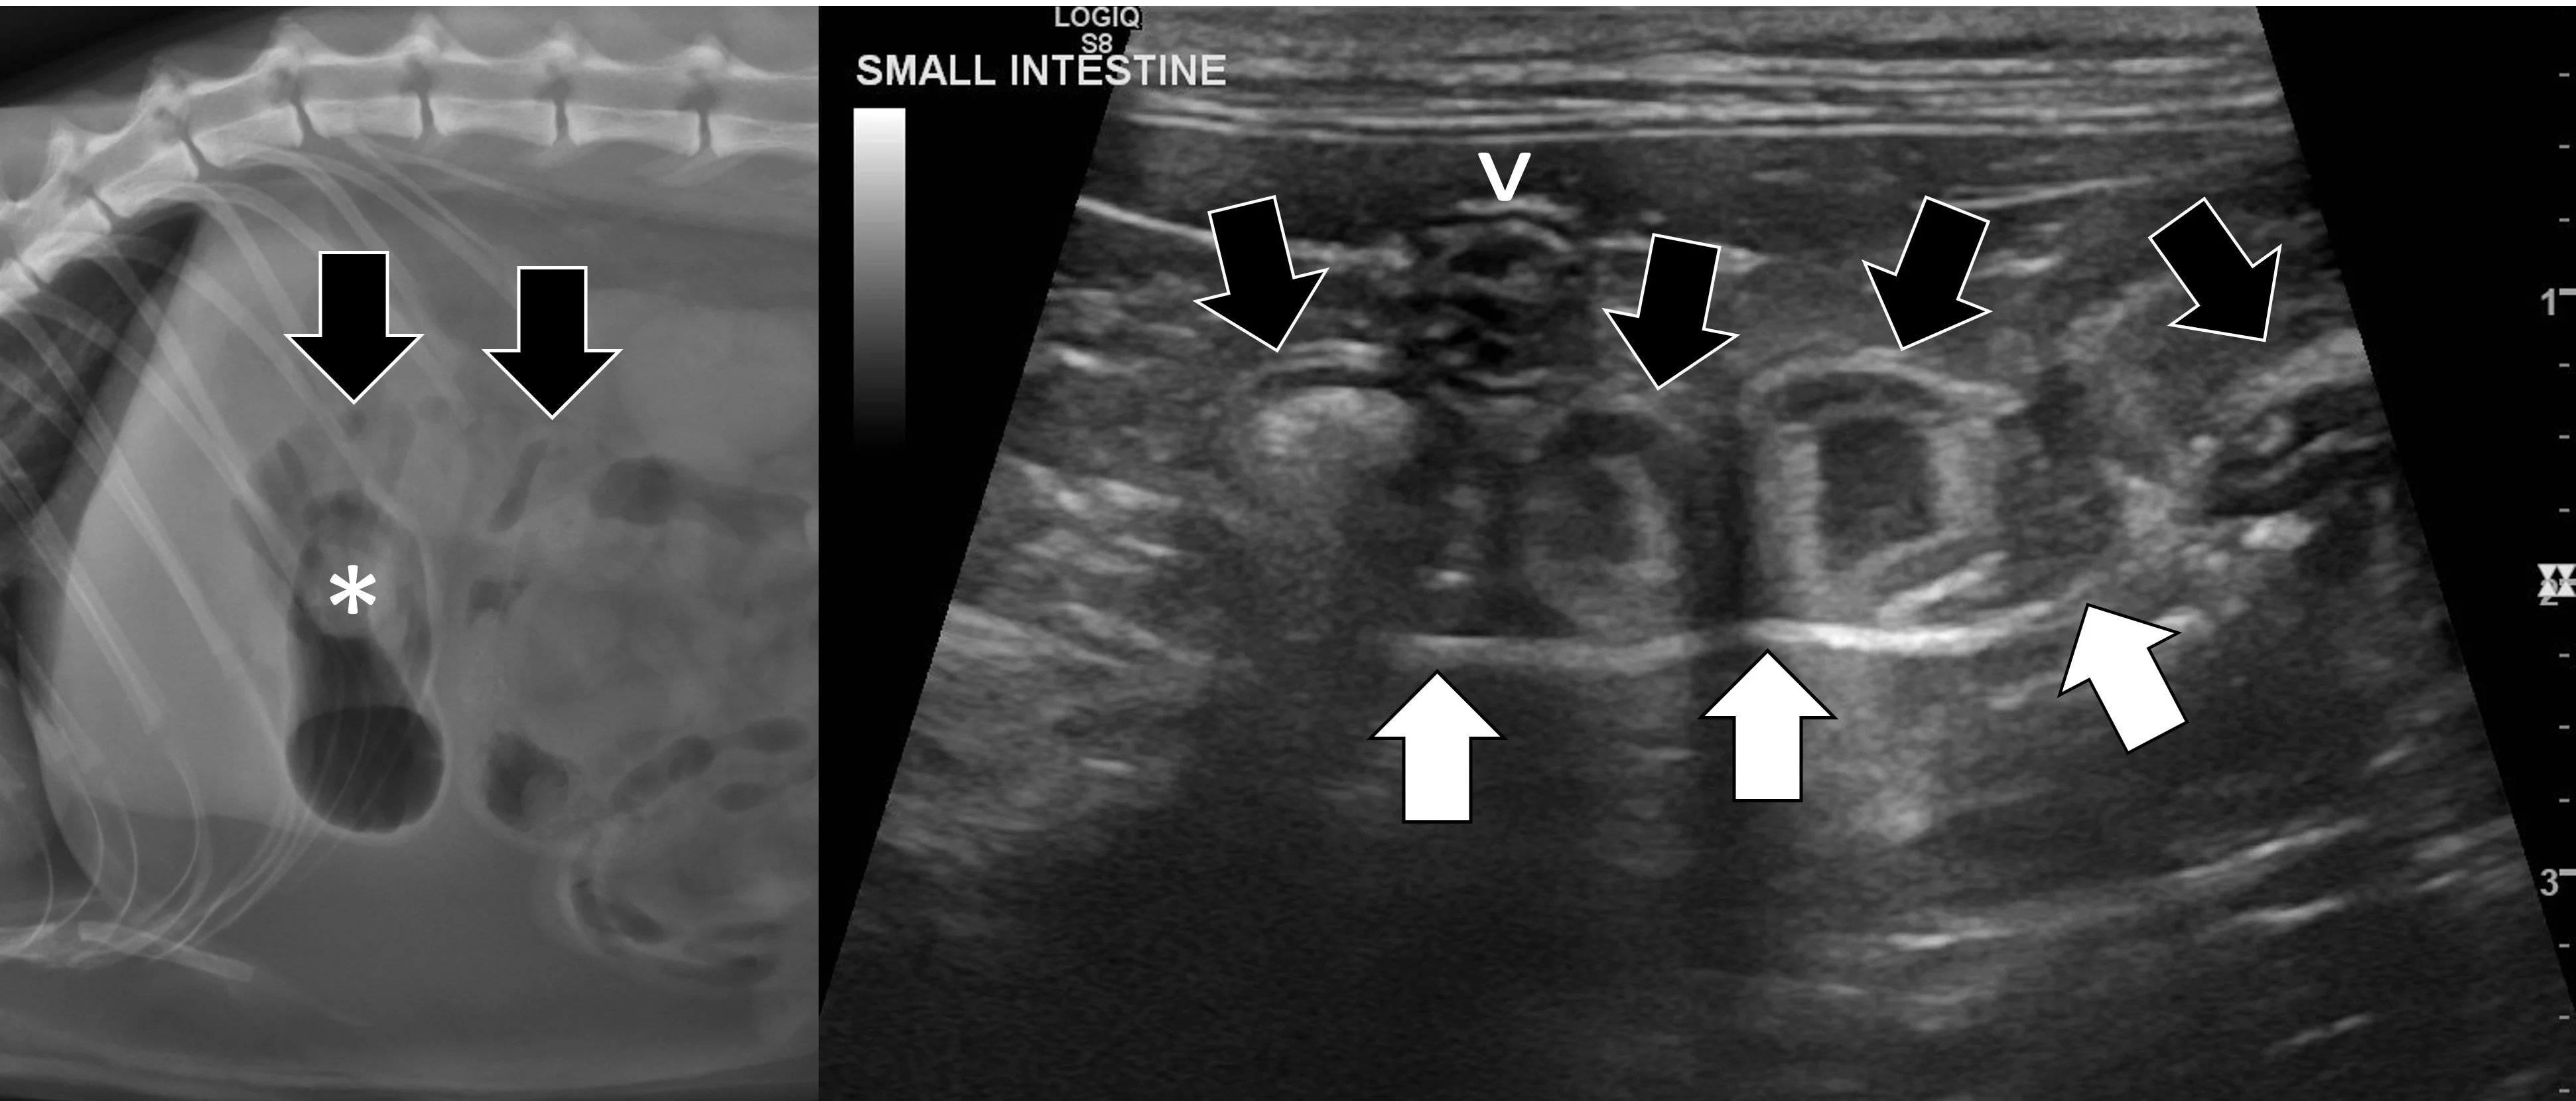

Pyloric outflow obstructions occur when a foreign body lodges in the pyloric outflow tract or the proximal duodenum and can cause variable gastric distention depending on the length of time the obstruction has occurred and whether the patient has recently vomited (Figure 2). Diagnosis of this type of obstruction via ultrasonography requires identification of an intraluminal structure that is causing gastric or proximal duodenal dilation orad to the foreign body.9-12 Foreign bodies are easier to see when surrounded by fluid. Although exceptions are possible, acute complete obstructions typically cause mild to moderate gas dilation, and chronic partial obstructions can cause more moderate to severe dilation, predominately with fluid.

FIGURE 2A

Abdominal ultrasound of a 3-year-old neutered male crossbreed dog with a surgically confirmed mechanical pyloric outflow obstruction. A homogeneously hypoechoic potato (asterisk) is present in the pylorus and completely visible due to its similar acoustic impedance as the surrounding soft tissues. There is transition from gas in the gastric lumen to the foreign body (white arrow). The remainder of the gastric lumen (pound sign) is not visible due to gas (black arrows) causing a hyperechoic surface with reverberation artifact.

Small intestinal mechanical obstructions occur when a foreign body blocks the lumen of any segment of the small bowel, causing segmental dilation located orad to the foreign body (Figure 3).9-12 As the small bowel increases in size, it crowds the peritoneal cavity and begins stacking on itself with sharp, hairpin turns.9-12 Dilated portions of the small bowel usually contain a mixture of fluid and gas. One study demonstrated that a serosal-to-serosal jejunal diameter of >1.5 cm helped discern dogs with and without mechanical obstruction.1 Dilated bowel can often be followed to the site of obstruction, where it immediately normalizes aborad to the foreign body. In some patients, the foreign body may not be visualized if located deep to more superficially located gas-dilated intestines. In patients scanned in dorsal recumbency, gravity may cause heavier foreign bodies to settle deep in the abdomen. If jejunal dilation >1.5 cm is present but the site of obstruction is not initially seen, the patient may be shifted into right and then left lateral recumbency and the midabdomen reinterrogated. In addition, one study suggested that a foreign body may be palpated in a majority of cases13; physical examination may therefore expedite ultrasonography. If the foreign body can be manually held or trapped against the body wall, ultrasonography can be performed on that location; however, identifying the site of obstruction is not always necessary if segmental dilation is present and the clinical picture supports a diagnosis of mechanical obstruction.

Abdominal ultrasound of a 9-month-old spayed Australian cattle dog with a surgically confirmed small intestinal mechanical obstruction. There is moderate small intestinal dilation (asterisk) with hyperechoic fluid, ingesta, and gas measuring 2.1 cm in diameter at the level of the white calipers oral to a pecan foreign body (pound sign) that is visible as a hyperechoic surface with distal acoustic shadowing. The small intestine is normal and not dilated immediately aboral to the foreign body (arrow), with a small volume of intraluminal gas causing reverberation artifact.

Linear foreign body obstructions occur when an object (eg, string, cloth) becomes stuck orally but extends aborally through the intestinal tract. Peristaltic contractions typically cause the small intestine to travel orally, eventually bunching. As a result, ultrasonographic findings include intestinal bunching (ie, plication) with or without a hyperechoic linear structure coursing through the lumen of the affected bowel (Figure 4).9-12 In some cases, trapped gas can cause a line that can be mistaken for the linear foreign body. Plication should not be confused with normal peristalsis or corrugation (Figure 5). With corrugation, the serosal margin is normal, and the mucosa and submucosa are undulant; with plication, the serosal margin is affected.14 In chronic cases, the mesentery surrounding the affected bowel may become hyperechoic, which can help identify the site of obstruction. Sterile inflammation and transudation may then result in focal accumulation of a small volume of free fluid. Mesenteric changes and peritoneal effusion also increase concern for bowel rupture and septic peritonitis. Patients may have concurrent findings of pyloric outflow or small intestinal mechanical obstruction, depending on the size and nature of the ingested cloth or string.

Abdominal ultrasound of an 11-month-old neutered male domestic shorthair cat with a surgically confirmed toy ball connected to a linear foreign body anchored in the pylorus (asterisk). The proximal duodenum is plicated (black arrows) with a hyperechoic linear structure (white arrows) coursing through the center. Normal small intestine can be seen adjacent to the plicated duodenum (caret).